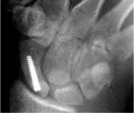

Scaphoid with Acutrak screw

Scaphoid Fracture